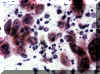

La citología es una

buena técnica para evaluar a un paciente que puede tener una infección

herpética. El fluido de una vesícula o la ulcera

reciente puede revelar el típico cambio de la morfología celular del

epitelio.

En la esquina de esta imagen se

observan células multinucleares con la cromatina condensada en la

periferia de los nucleos hipocromáticos.